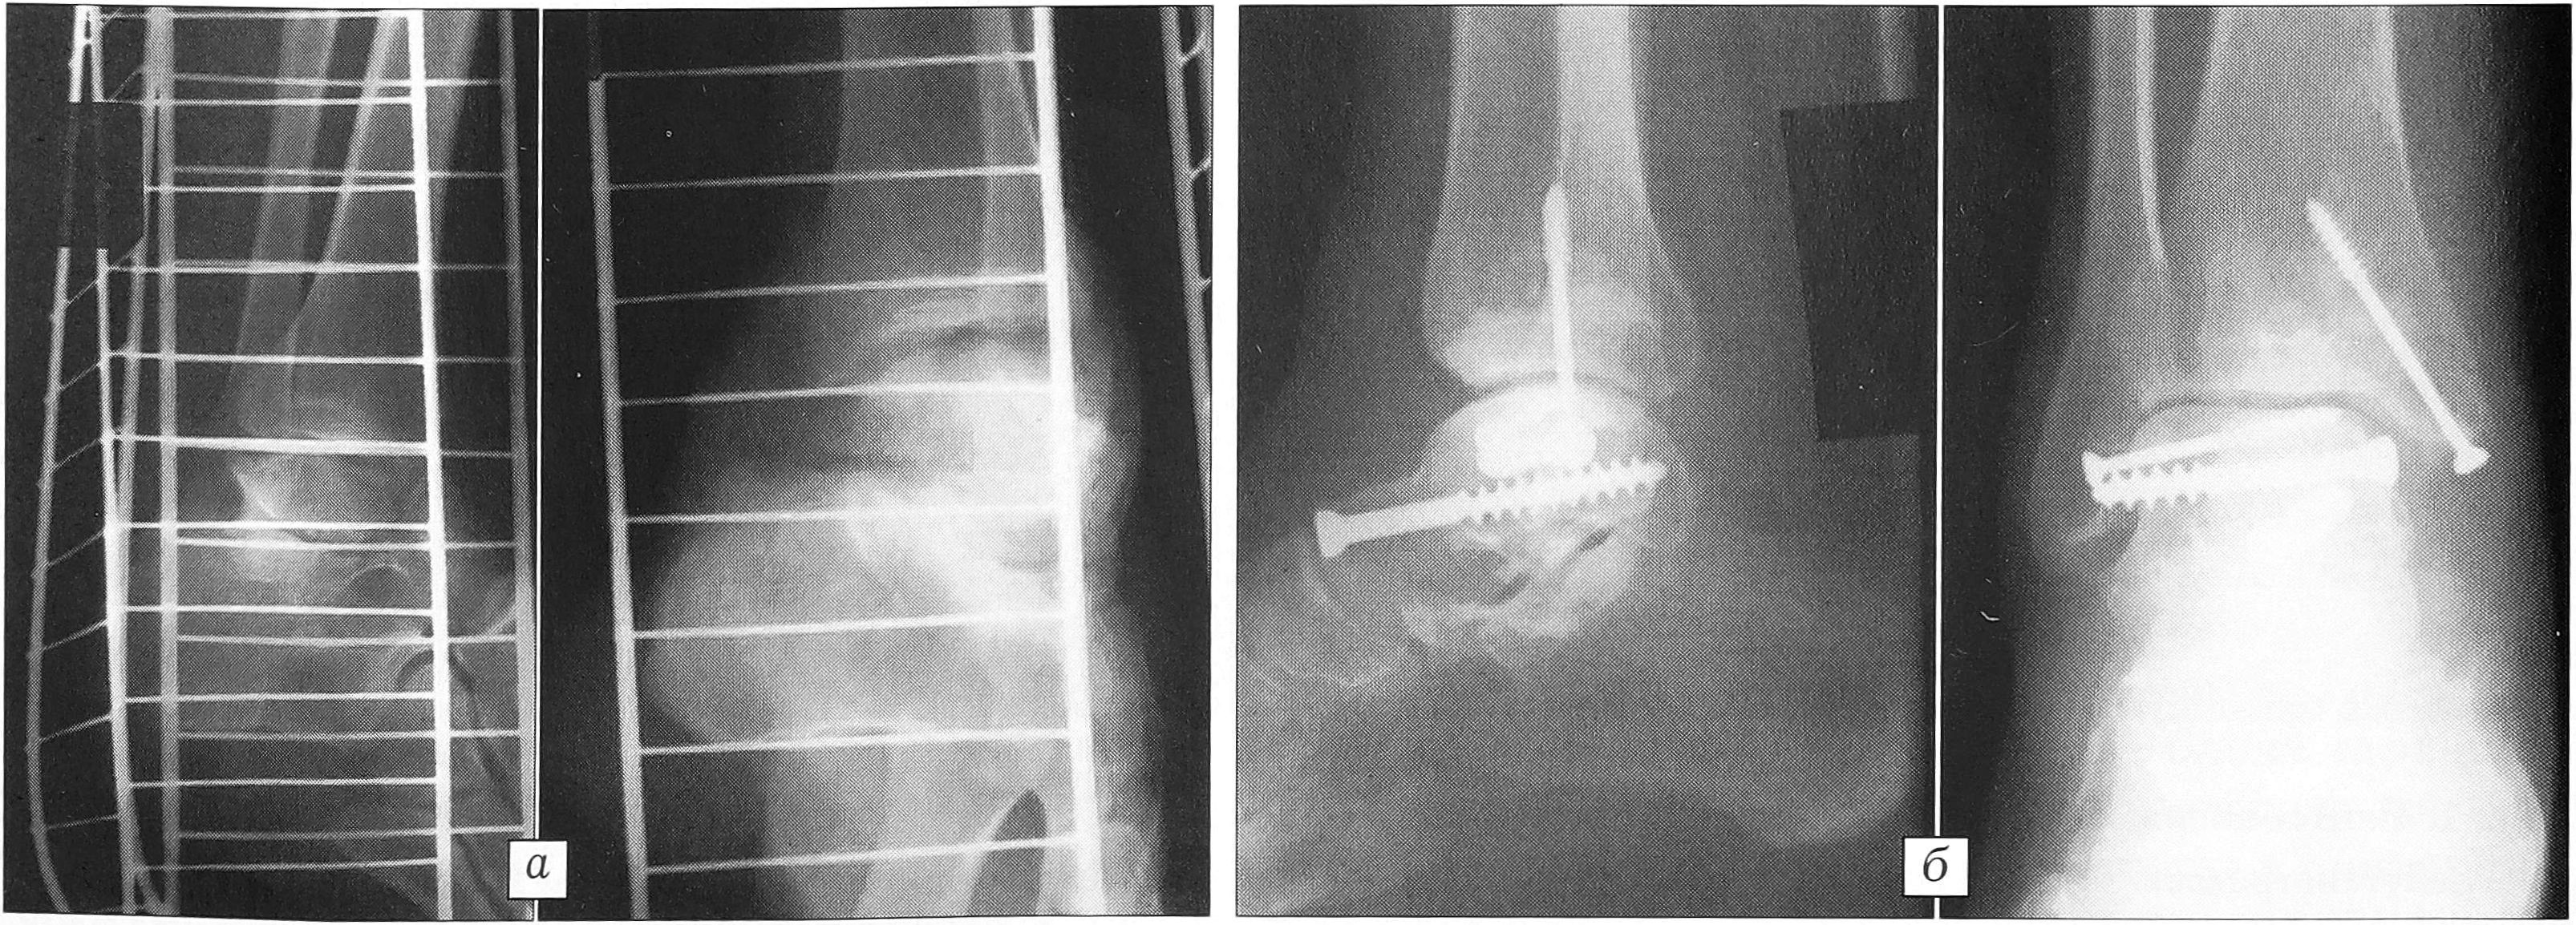

Пример 1. Больной А., 31 года, получил травму на производстве: оступившись, упал с высоты 1,5 м. Госпитализирован с диагнозом: закрытый перелом блока таранной кости правой стопы (рис. 1, а). Наложена система демпферированного скелетного вытяжения за пяточную кость. Для определения степени и вида разрушения таранной кости, кроме рентгенографии в типичных укладках, произведена компьютерная томография. Диагноз уточнен: закрытый оскольчатый перелом блока и тела таранной кости во фронтальной и сагиттальной плоскостях (рис. 1, б, в). Примечательно, что продольный перелом (в сагиттальной плоскости) на типичных рентгенограммах не выявляется. Больной оперирован на 3-и сутки. Медиальный доступ с отсечением внутренней лодыжки. Выполнен остеосинтез отломков блока таранной кости четырьмя винтами. Внутренняя лодыжка фиксирована двумя винтами (рис. 1, г). Послеоперационное течение без осложнений. Контрольный осмотр через 3 мес после операции: пациент ходит с помощью трости, болей, отеков нет. На контрольных рентгенограммах признаков асептического некроза таранной кости не выявлено. Приступил к труду без ограничений через 4 мес. Винты из таранной кости удалены через 11 мес, один винт при удалении сломался (рис. 1, д).

Рис. 1. Рентгенограммы и компьютерная томограмма больного А. а — рентгенограммы при поступлении; б, в — КТ во фронтальной проекции при поступлении: б — многооскольчатый перелом внутреннего края тела таранной кости, в — хорошо виден перелом тела таранной кости, проходящий в сагиттальной плоскости, с интерпозицией мелких костных осколков; г — рентгенограммы после открытой репозиции и фиксации таранной кости четырьмя винтами; д — рентгенограммы при удалении металлоконструкций: в блоке таранной кости виден сломавшийся винт, внутренняя лодыжка фиксирована вновь.